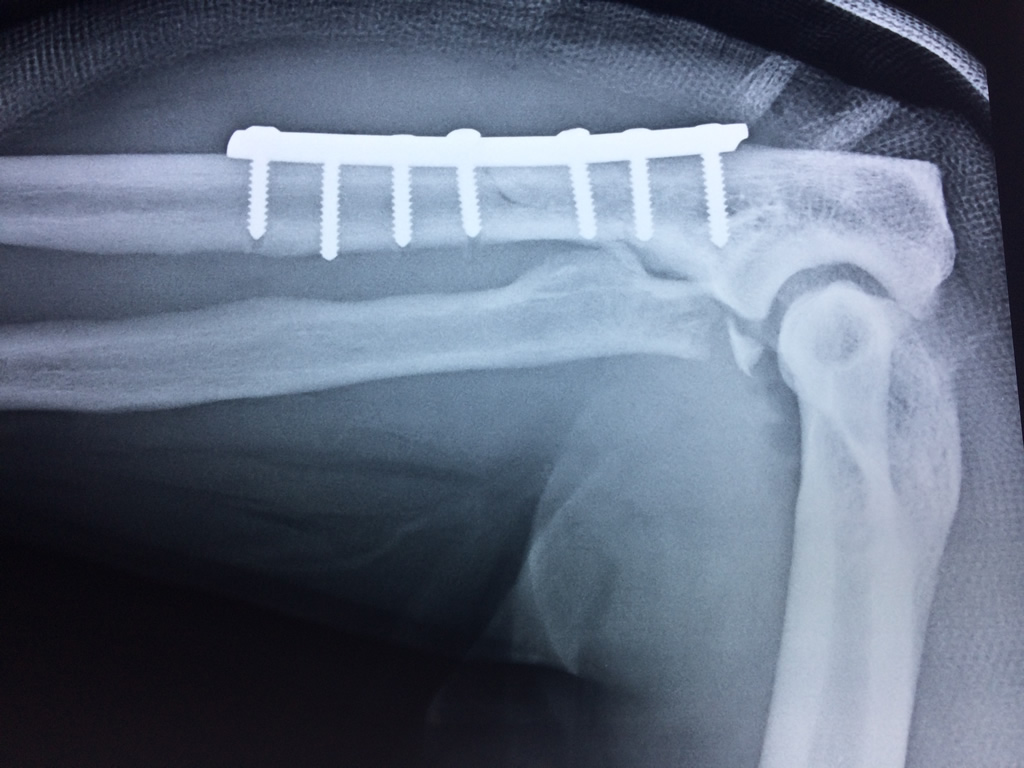

Los extremos óseos se conectan entre si por un conjunto de ligamentos que contribuyen a su fijación y están rodeado por una estructura común que se llama cápsula articular, en cuyo interior se encuentra el líquido sinovial.

En el lenguaje común se le da el nombre de codo a la parte posterior y prominente situada en la unión del brazo con el antebrazo.